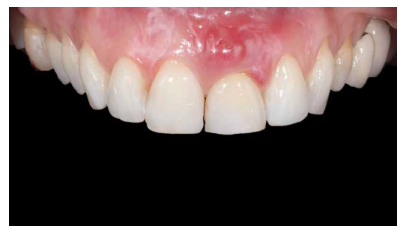

Caso clínico: Se presenta el caso de una paciente mujer de 32 años de edad, que acude por presentar una posible fractura radicular del incisivo central superior izquierdo (ICSI), acompañada de la aparición de un absceso periodontal en la región del fondo de vestíbulo de dicho diente. Tras llevar a cabo la exploración clínica y radiológica, se establece que el pronóstico del ICSI es desfavorable para llevar a cabo un tratamiento conservador del mismo. Tras la valoración de las características clínicas del caso presente, el plan de tratamiento se inclinó por la realización de la exodoncia del ICSI con la colocación simultánea de un IOI postextracción y la carga inmediata con una prótesis provisional del mismo.

Clinical case: We present the case of a 32-year-old female patient who presented with a possible root fracture of the upper left central incisor (ULCI), accompanied by the appearance of a periodontal abscess in the region of the bottom of the vestibule of said tooth. After carrying out the clinical and radiological examination, it is established that the ULCI prognosis is unfavourable for carrying out conservative treatment of the tooth. After assessing the clinical characteristics of the present case, the chosen treatment plan was to extract the ULCI with the simultaneous placement of a post-extraction osseointegrated implant (OII) and immediate loading of a provisional prosthesis on the implant.